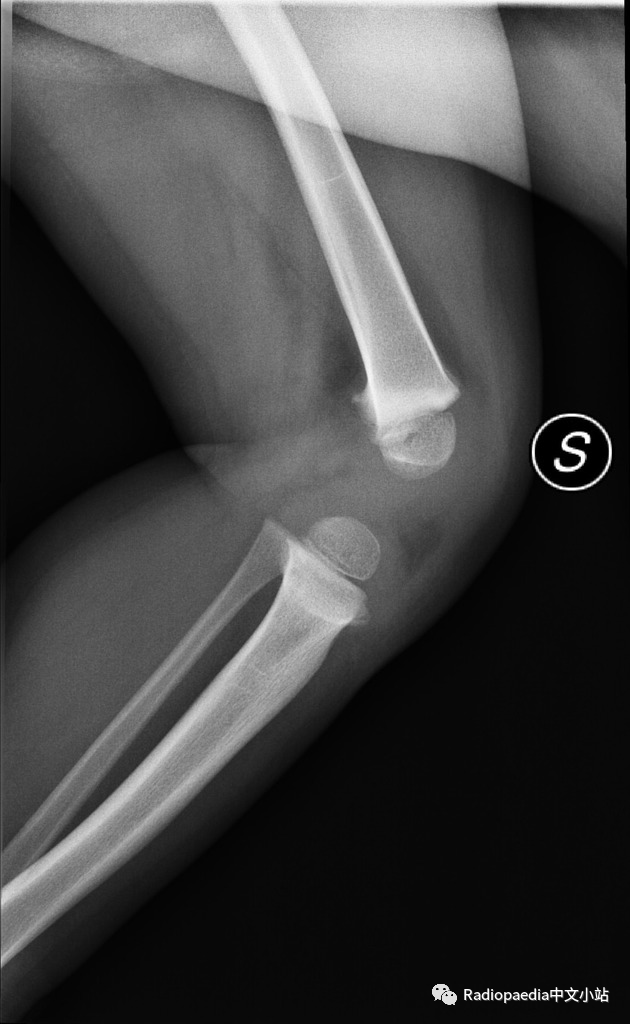

Blount病(胫骨内翻)是一种累及胫骨近端的进行性畸形,发病机制可能是由于胫骨近侧骺板的内后方受到应力,导致生长板发育障碍。该病分为婴儿型和青少年型。

婴儿型Blount病,常为双侧受累(60~80%),但双侧多不对称。多有家族史,见于1~3岁婴幼儿,危险因素是过早走路和肥胖。需要与生理性弯曲相鉴别。

当临床出现进展性内翻,同时平片中胫骨近端出现特征性改变(干骺端内侧增宽、规则,骨皮质增厚且呈垂直走形呈鸟嘴样;内侧骨骺高度减小)时可以明确诊断。